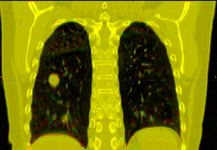

Image:PETCTFusion.png| [[Modules:PETCTFusion-Documentation-3.6 |PETCTFusion]] (Wendy Plesniak) | Image:PETCTFusion.png| [[Modules:PETCTFusion-Documentation-3.6 |PETCTFusion]] (Wendy Plesniak) | ||

PETCTFusion (Wendy Plesniak)